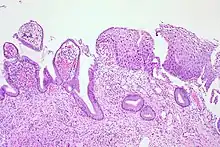

CIN is classified in grades:[14]

| Histology Grade | Corresponding Cytology | Description | Image |

|---|---|---|---|

| CIN 1 (Grade I) | Low-grade squamous intraepithelial lesion (LSIL) |

|

![]() |

| CIN 2/3 | High-grade squamous intraepithelial lesion (HSIL) |

| CIN 2 (Grade II) |

![]() | |

| CIN 3 (Grade III) |